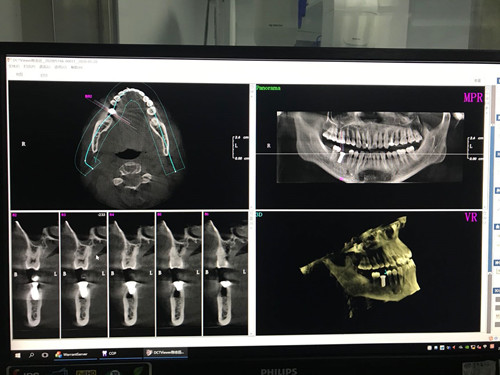

洪礼琳介绍,通过术前计算机的精准设计、术中同步的导航、术后及时的验证,做到微创、精准,同时避免了对患者术区周围重要组织的损伤,使患者收获了满意的疗效。导航系统的使用使精准的种植牙手术省去了以往需要制作种植导板等费时费力的过程,只需要,将合适的种植体在CBCT显示的影像中放置于缺牙区合适的位置,将患者CBCT导入导航系统中,术中导航系统利用自带的红外线识别装置,识别种植手机的位置,从而指导种植手术在精准的位置、深度上进行。

洪礼琳分享了使用导航系统的心得:导航系统用于种植手术中,犹如在开车过程中使用定位系统一样,可以在行为之前就设定好行为的全过程,并在行为中,误差发生时,按照设定好的路线来指导具体操作。不仅能全盘掌控手术,同时也能达到微创,使患者受到较小的创伤,获得良好的就医体验。与此同时也能通过计算机上设计好的方案,使患者更直观的看到种植体的位置,减轻了对种植手术的恐惧心理。